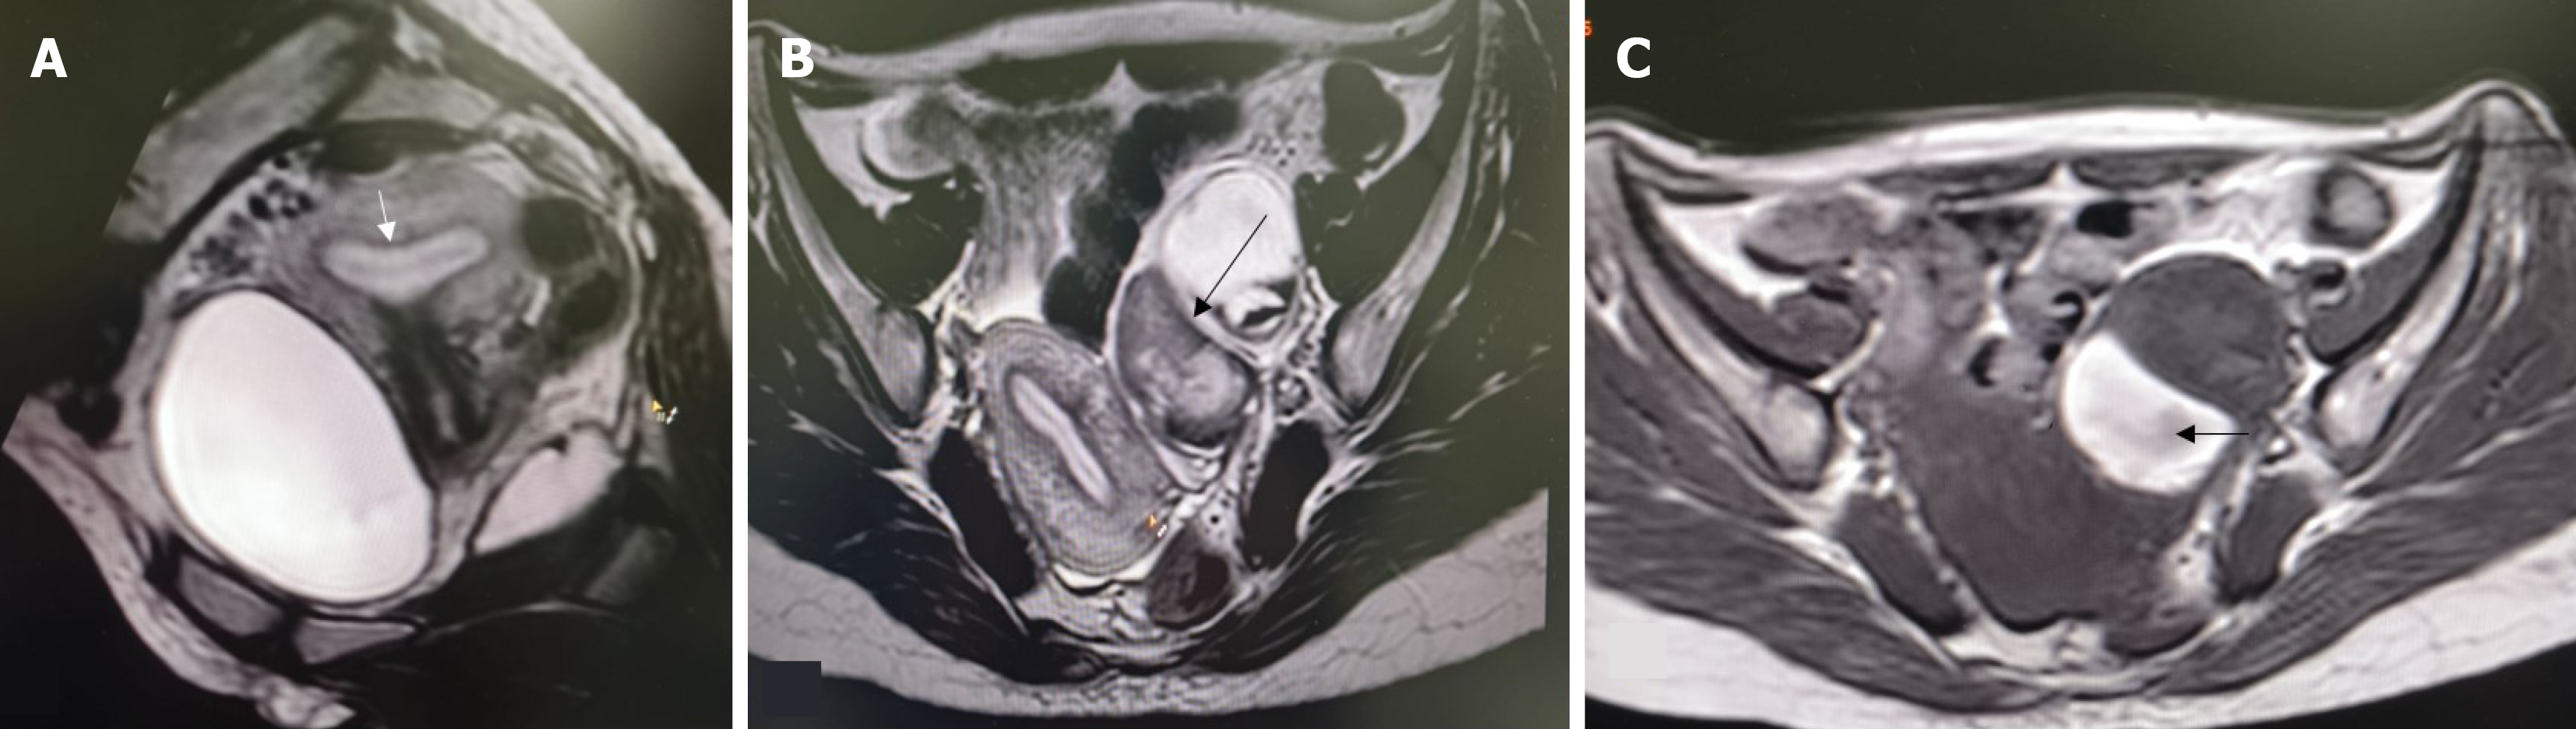

Overall, 22 patients had MRI findings consistent with endometriosis. Peritoneal disease (P1-P3) was not identified in this series. Ovarian endometriomas were present in 16 patients (21.3%), most commonly in the 3-7 cm range (O2, 12 patients; 16.0%). Tubo-ovarian adhesions or involvement (T2-T3) occurred in 11 patients (14.7%) (Figures 1, 2 and 3). Deep endometriosis nodules were observed primarily in the parametrial/uterosacral compartment (B) in 6 patients (8.0%). No rectosigmoid (C) or anterior compartment (A) endometriosis lesions were seen. Adenomyosis was identified in 4 patients (5.3%; diffuse in 2, focal in 2). A summary is presented in Table 2.

Table 3 highlights the association between uterine anomaly type, outflow obstruction, and the presence of endometriosis. Endometriosis was more frequently observed in patients with complex uterine anomalies, particularly U3c (bicorporeal septate uterus), U5a (aplastic uterus with a functional rudimentary cavity), and U0 (arcuate uterus), whereas a markedly low prevalence was noted in U5b (aplastic uterus without a functional cavity). A statistically significant association was seen between uterine category and endometriosis (P = 0.006).

With respect to associated anomalies, vaginal aplasia (V4) showed a significantly lower prevalence of endometriosis compared to patients with a normal vagina (P = 0.019), while cervical anomaly subtype did not demonstrate a statistically significant association. Overall, these findings suggest that functional endometrial tissue combined with altered outflow or complex uterine morphology plays a key role in determining the distribution of endometriosis in patients with Mullerian anomalies. Patients with a rudimentary horn containing a functional cavity had a significantly higher prevalence of endometriosis compared to those without a rudimentary horn (66.7% vs 26.1%, P = 0.036).

Among the 75 patients evaluated, obstruction was identified in 13 patients (17.3%). Within uterine anomaly groups (U), obstruction was most frequent in U3c anomalies, where 6 of 13 patients (46%) demonstrated obstruction. The presence of genital tract obstruction showed a strong correlation with endometriosis, with affected patients demonstrating nearly threefold higher prevalence compared to those without obstruction (61.5% vs 22.6%, P = 0.005). In this subgroup, obstruction affected both endometriosis (3/7; 43%) and non-endometriosis (3/6; 50%) patients. In U0 uteri (arcuate), 2 of 4 patients affected (50%), split equally between endometriosis (1/3) and non-endometriosis (1/1). U4a had obstruction in 1 of 2 patients (50%), single patients showed signs of obstruction in each group of U4b, U5a, U6. It was rare in U2a (1/14; 7%) and U5b (1/25; 4%). Across cervical categories (C), obstruction occurred predominantly in patients with normal morphology (C0), where 10 of 29 patients (34.5%) had endometriosis. In C2, 7 of 14 patients had endometriosis, whereas severe anomalies (C4) were associated with endometriosis in 4 of 29 patients (13.8%). Despite these endometriosis distributions, obstruction overall remained infrequent and did not cluster within any specific cervical subtype. Vaginal morphology similarly showed limited correlation with obstruction. Most patients with normal vaginal anatomy (V0) did not exhibit obstruction, despite 18 of 46 having endometriosis (39.1%). Among those with V4 anomalies, endometriosis was identified in 4 of 29 patients (13.8%). Overall, obstruction occurred sporadically across uterine, cervical, and vaginal classifications. Obstruction was most frequent in U3c (46% of that subgroup) but was distributed among both endometriosis and nonendometriosis patients.